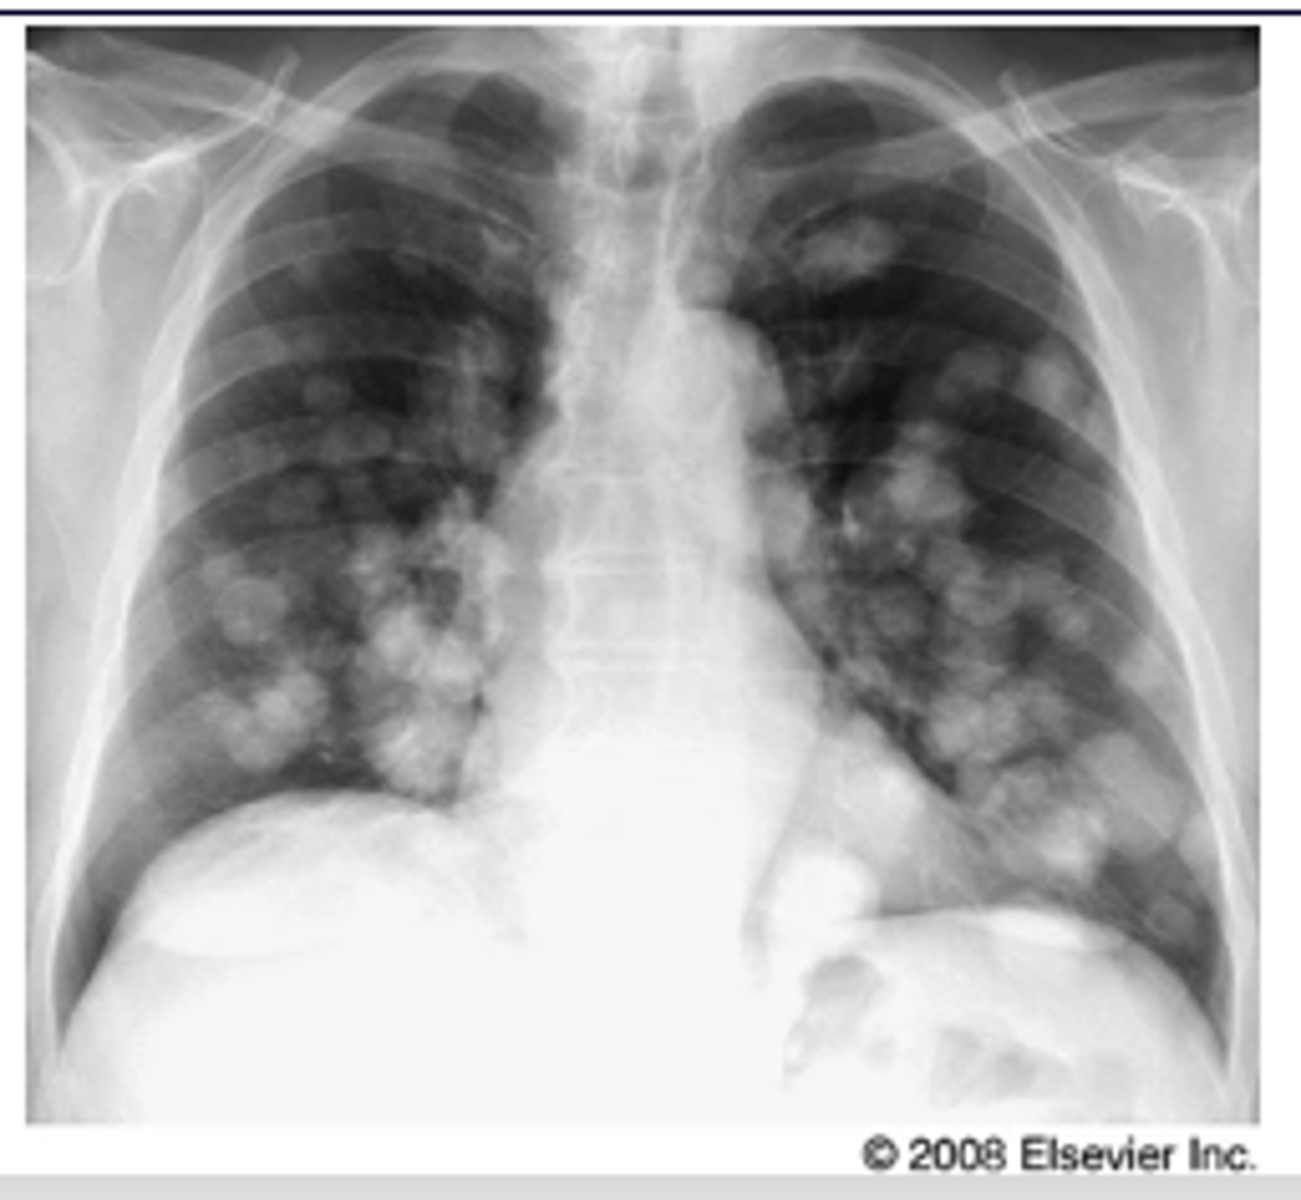

What will metastatic dz look like on radiograph?

Nodular pattern resulting from multiple small metastases to the lung from a colonic adenocarcinoma

<p>Nodular pattern resulting from multiple small metastases to the lung from a colonic adenocarcinoma</p>